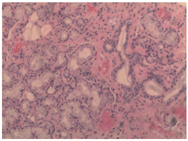

12月4日患者转入神经内科监护室,再次复查腰穿脑脊液压力260 mmH2O,蛋白1.29 g/L,糖和氯化物正常,细胞数50×106/L(单核比例98%),具体腰穿检查结果见表1,细胞学检查提示淋巴细胞反应,送检中枢神经系统感染病原微生物高通量基因检测、自身免疫性脑炎、MOG抗体、副肿瘤综合征抗体、寡克隆带、抗酸杆菌涂片、阿利新蓝染色均为阴性。血清病毒学中EB病毒衣壳抗原IgM(62 U/ml)、单纯疱疹病毒Ⅰ型IgG、巨细胞病毒IgG、EB病毒衣壳抗原IgG和肺炎衣原体IgG均为阳性,脑脊液病毒学抗体均为阴性。完善头颅静脉窦核磁成像未见明显异常,红细胞沉降率70 mm/h,肿瘤标志物、甲功、糖化血红蛋白等均未见明显异常,风湿免疫性抗体中可见ANA阳性,滴度1∶100,颗粒+浆粒型,抗dsDNA IgG型25.9(<20)U/ml,抗SSA IgG型(+),抗Ro-52 IgG型(++),抗线粒体抗体2型IgG型(+++),抗M2-3E(BPO)IgG型(+++)。经风湿免疫科建议后行腮腺同位素造影提示双侧腮腺及双侧颌下腺功能正常,唇腺活体组织检查提示间质内见3处淋巴细胞浸润灶,其中1灶淋巴细胞数目大于50个/灶(图2)。眼干三项滤纸试验右眼9 mm,左眼4 mm,角膜荧光染色双侧阳性,泪膜破裂时间右侧5 s,左侧4 s。诊断考虑干燥综合征相关的脑膜脑炎,治疗于2020年12月22日开始给予甲泼尼龙48 mg/d,白芍总苷胶囊0.6 g/次,2次/d,硫酸羟基氯喹200 mg/次,1次/d。患者治疗的第4天,患者头痛发热症状明显好转。2021年1月4日复查腰穿压力180 mmH2O,细胞数下降至14×106/L。2021年1月6日出院,出院后患者继续口服甲泼尼龙48 mg/d,计划每2周减半量,其余药物剂量同前。2021年4月随访患者未再出现发热及头痛症状,已恢复正常生活,复查红细胞沉降率9 mm/h,ANA阴性,滴度<1∶10,抗dsDNA IgG型、抗SSA IgG型、抗Ro-52 IgG型、抗线粒体抗体2型IgG型和抗M2-3E(BPO)IgG型均已转为阴性。